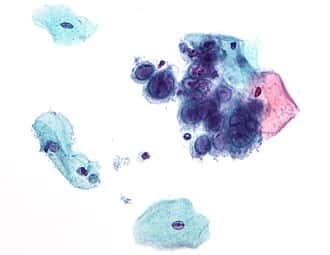

Micrograph showing the viral cytopathic effect of herpes (ground glass nuclear inclusions, multi-nucleation). Pap test. Pap stain.